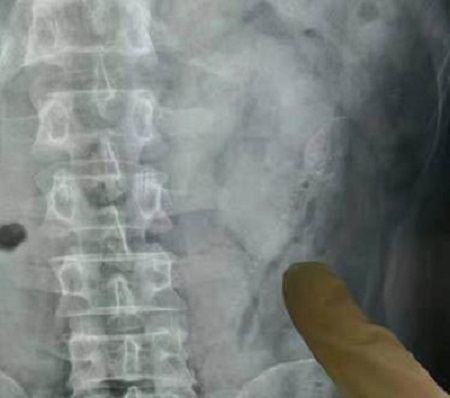

Scans show one of the fish inside the man’s body before the operation

Scans revealed one of the creatures – measuring 4in and 6in respectively – had broken through the wall of his bowel.